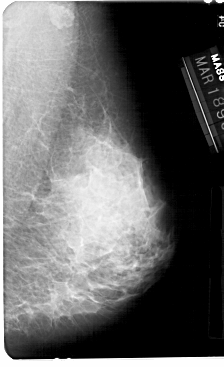

A_1361_1.LEFT_MLO

LEFT_MLO LINES 5491 PIXELS_PER_LINE 3346 BITS_PER_PIXEL 12 RESOLUTION 43.5 OVERLAY